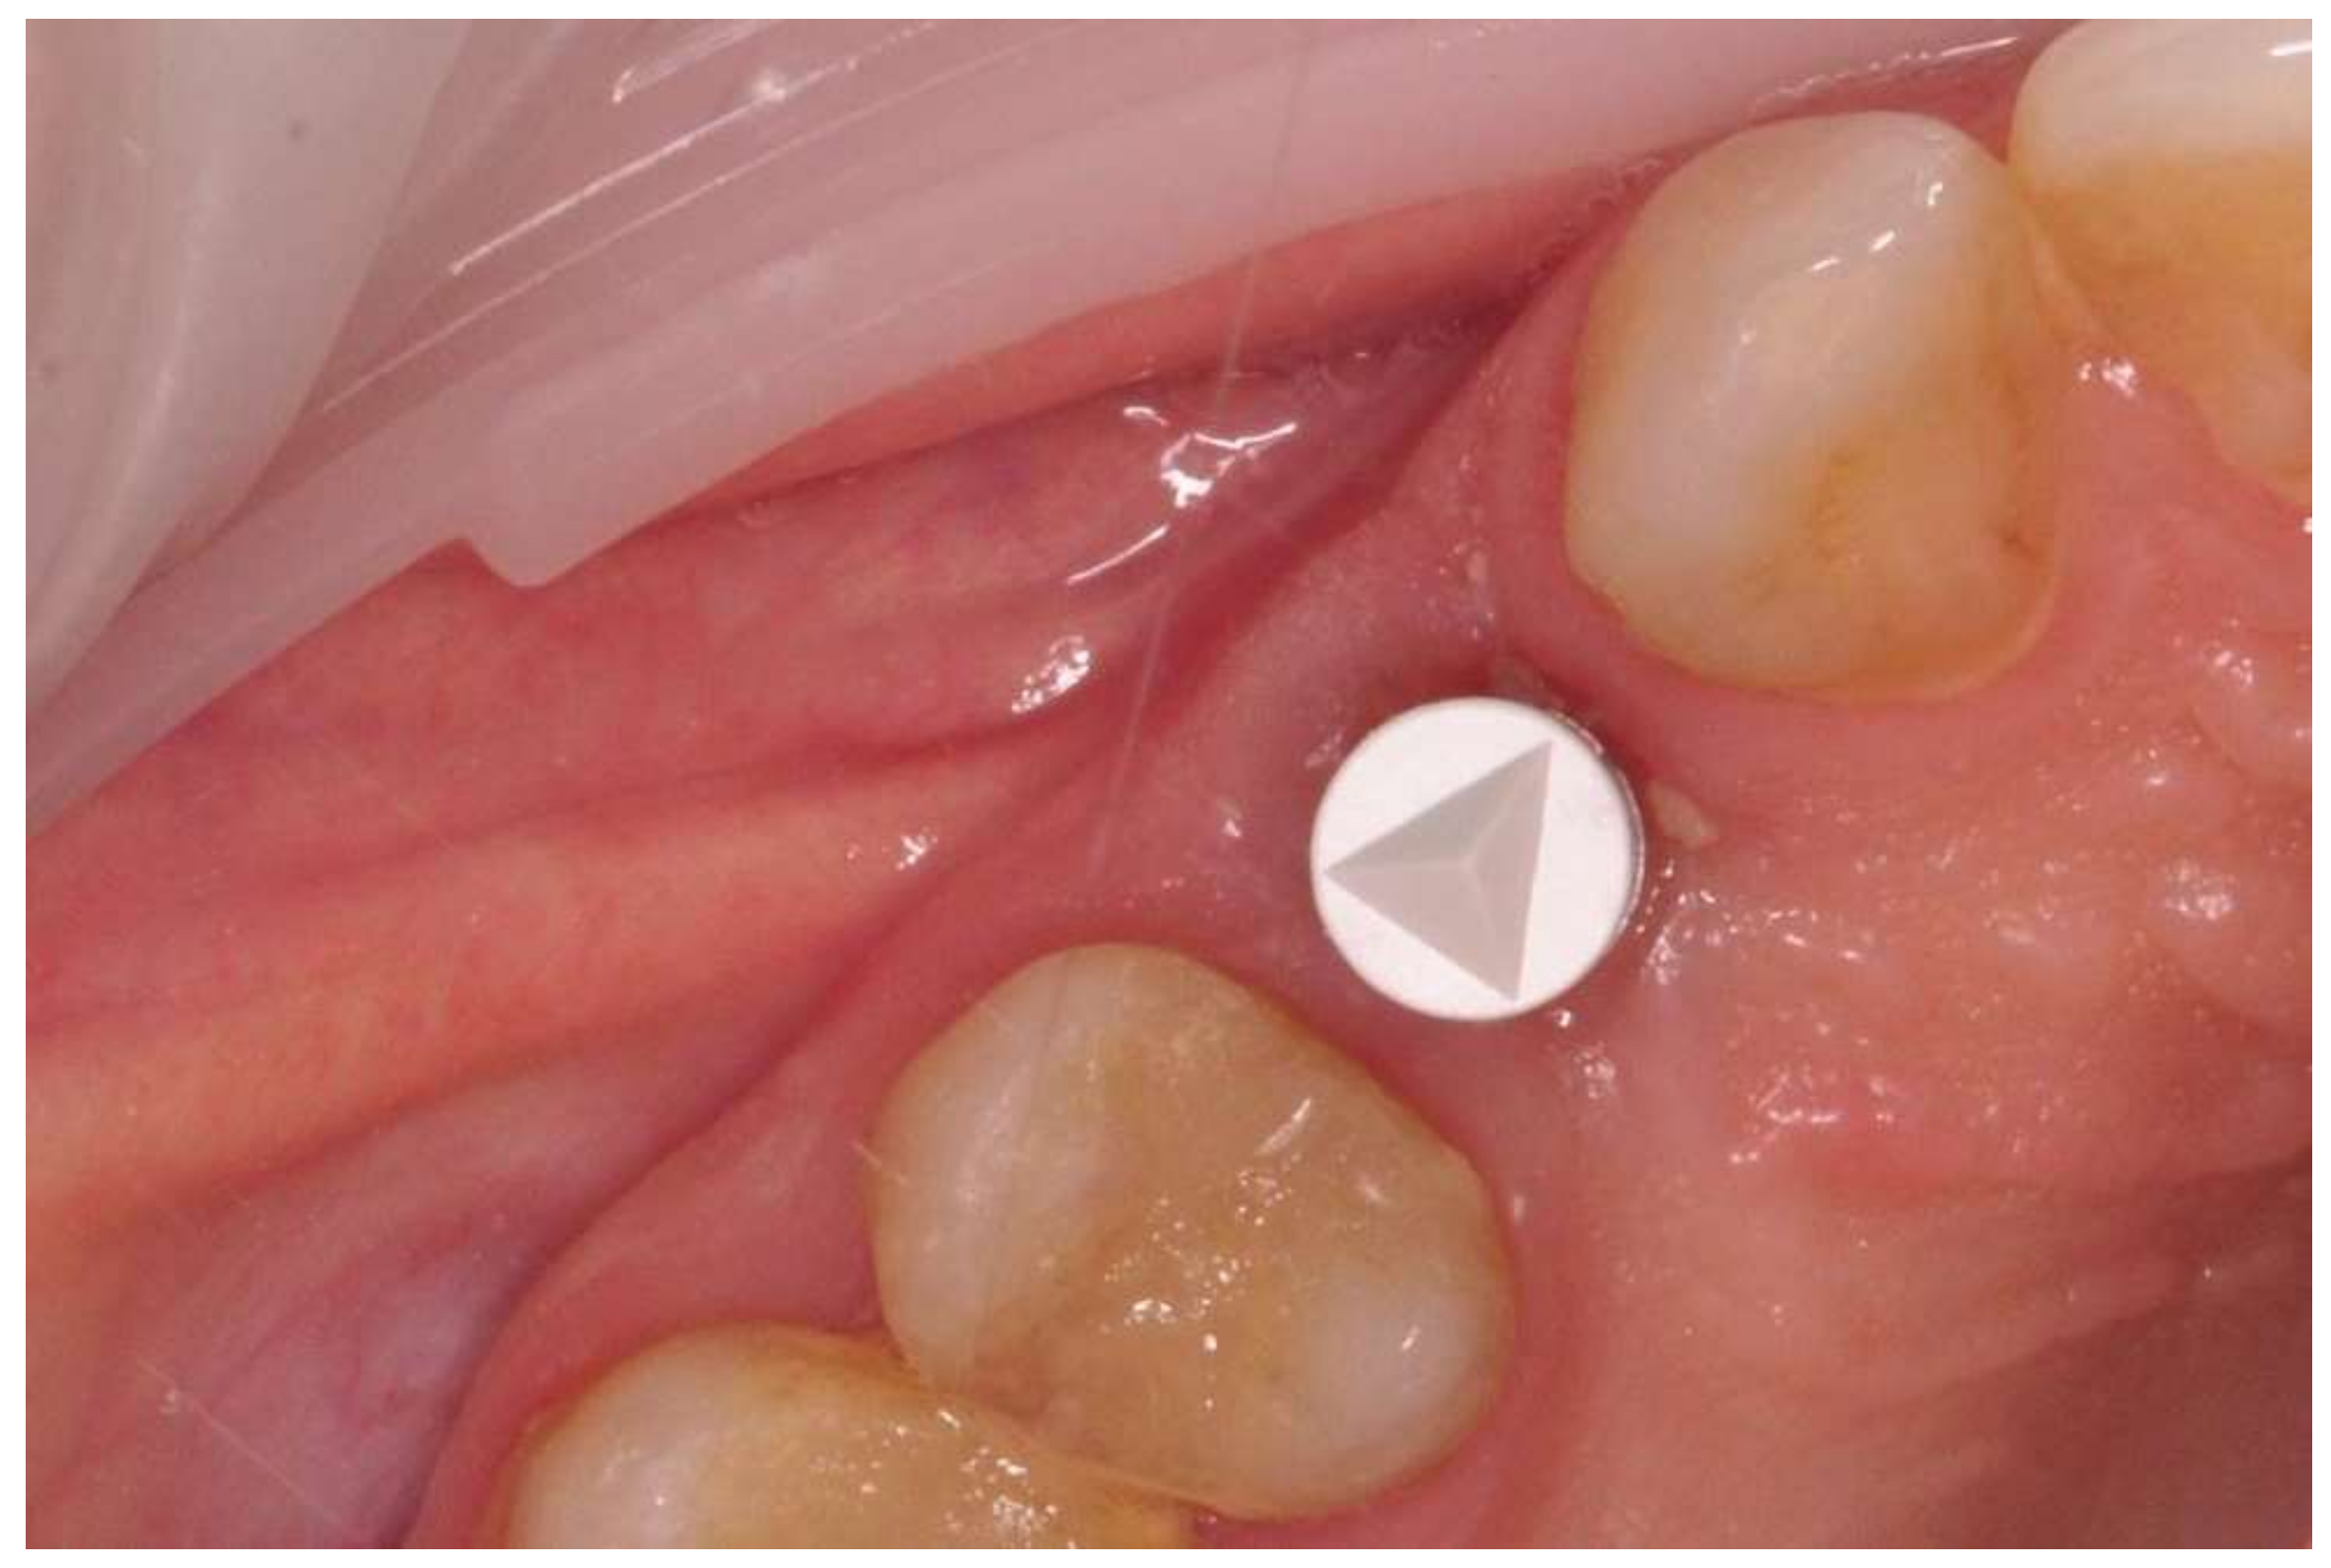

The prosthetic restoration stage started 4 weeks after the implant placement surgery and was prepared in the chairside laboratory by W.G. Patients with no signs of inflammation in the direct vicinity of the implant and with an ISQ (implant’s stability quotient) value of 65 or greater were allowed to participate in the prosthetic protocol. The measurements using the aforementioned device were performed three times in the mesiodistal, buccal and palatal, as well as periapical direction, and the smallest value was considered the cut-off point. Screw-retained implant crowns made of lithium disilicate glass-ceramics, IPS e max CAD LT (Ivoclar Vivadent AG, Schaan, Liechtenstein), were used as the prosthetic restoration materials. After the removal of the healing abutment, the implant bed was cleaned. The scans were taken with an intraoral scanner Sirona Cerec AC Bluecam (DentsplySirona, York, PA, USA) (Figure 2). Subsequently, the crown internal surface was etched and then fixed using Multilink Hybrid Abutment cement (Ivoclar Vivadent AG, Schaan, Liechtenstein) on the previously sandblasted titanium base (TiBase) for Sirona Cerec (DentsplySirona, York, PA, USA). The crown was then screwed onto the implant with a force of 25 Ncm. The occluding relations were controlled using articulating paper (Bausch®, Cologne, Germany) with a thickness of 200, 80, and 8 μm. The hole was filled in with Gradia composite (GC Corporation, Tokyo, Japan) and an RVG image was taken (Figure 3). The patients were instructed on proper hygiene around the dental implant.

Figure 2. Implant with scanbody prepared for intraoral scan.

Figure 3. Implant loaded with the screw-retained crown.